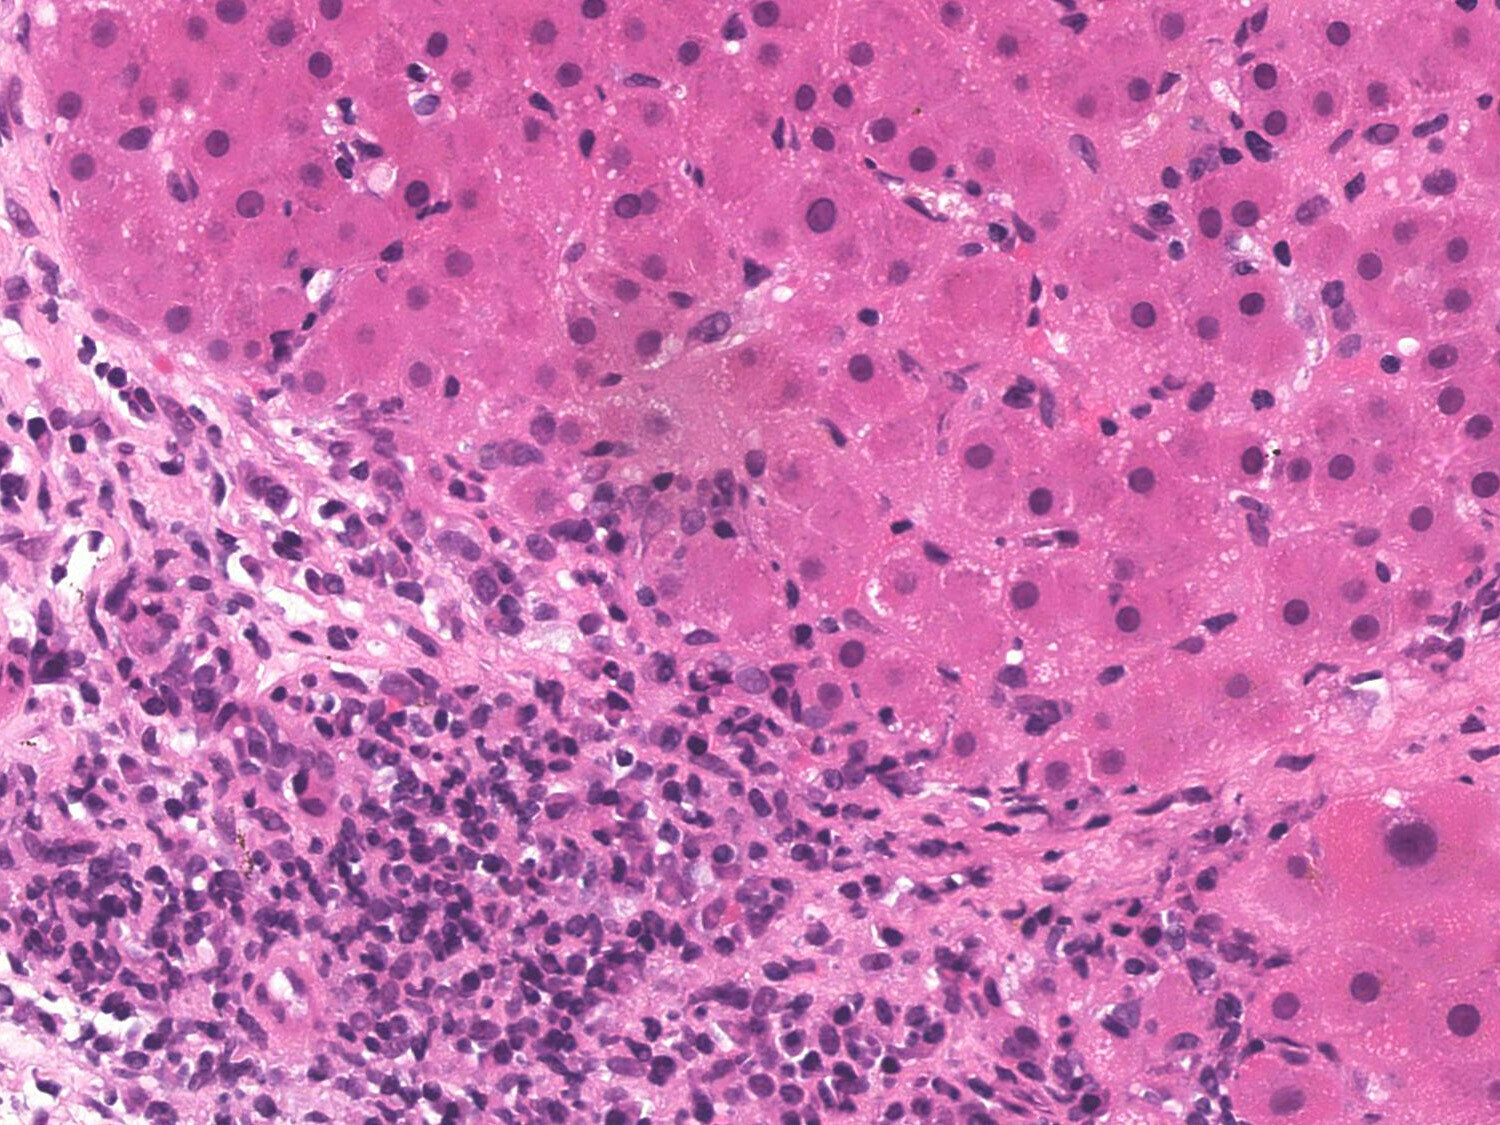

hepatocellular carcinoma